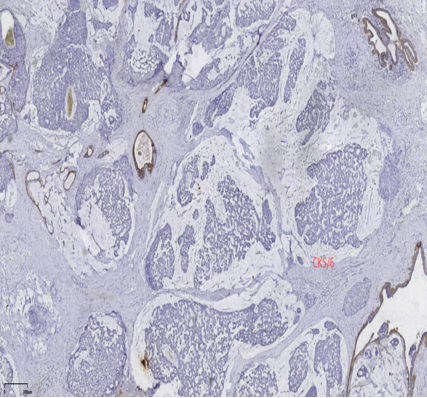

CK5/6、CKH-,可斑驳性的残留

肌上皮内-,导管周可-可+